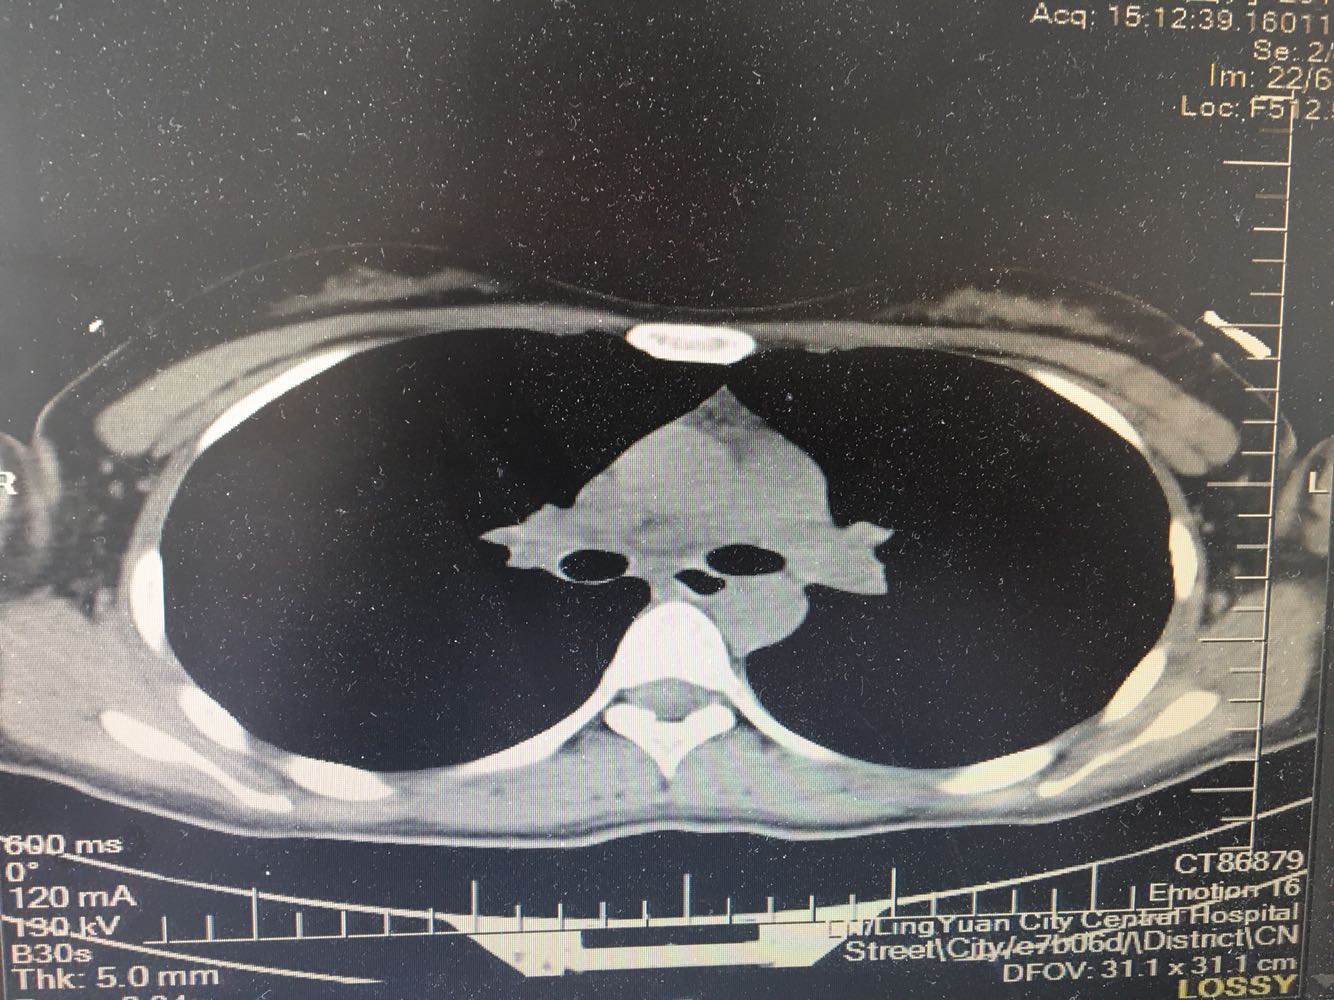

女,26岁,咳嗽1周,咳痰不畅,咽喉痒,口服阿莫西林无好转,昨日发热,体温38.5摄氏度,于门诊查肺CT后以肺炎收入院,病来无盗汗,无咳血,无消瘦及乏力,无头痛,无肢体酸痛,饮食睡眠可,二便正常

支原体肺炎?肺结核?

支原体抗体1:160,结核抗体弱阳性。支原体肺炎个别可见上叶病变,该患无结核中毒症状,考虑支原体肺炎可能性大,但肺尖为结核好发部位,需要抗炎治疗后复查观察疗效。